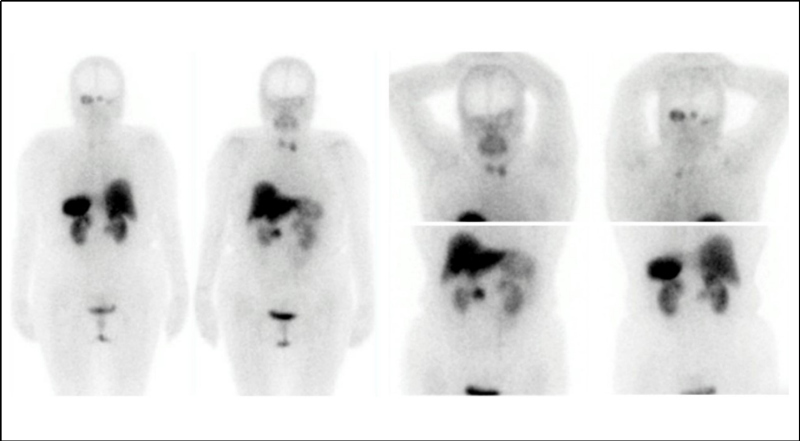

En las imágenes planares se observan múltiples áreas de captación anormal en la fosa posterior y en el aspecto lateral del hilio renal derecho (fig. 1). Se identifican tres lesiones cerebelosas con componente sólido realzante y quístico, altamente vascularizadas, que presentan aumento de perfusión y generan edema extenso obliterando el cuarto ventrículo, consistentes con hemangioblastomas (fig. 2). Existe otra lesión que genera invasión ósea de la mastoides con compromiso del oído interno; en la RM es isointensa e hiperintensa en las secuencias T1, hiperintensa en las secuencias T2, con captación del medio de contraste, por tumor del saco endolinfático (fig. 2). En la valoración de la cavidad abdominal se detecta una lesión sólida en la cabeza/proceso uncinado del páncreas, hipodensa respecto al resto del parénquima, compatible con tumor neuroendocrino (fig. 3).

El protocolo de seguimiento de los pacientes con hemangioblastomas cerebrales se realiza mediante RM contrastada cerebral y de columna total dos veces al año en pacientes desde los 11 años y con examen físico y neurológico anual. La vigilancia de las anormalidades abdominales requiere un ultrasonido abdominal anual y RM de abdomen bi-anual en pacientes mayores de 16 años(2). El papel de la gammagrafía con análogos de la somatostatina no sólo es importante para el diagnóstico y caracterización de lesiones pancreáticas que expresan estos receptores(4), sino también para la valoración de otras lesiones, en este caso particular de las localizadas en el SNC. Estos hallazgos pueden potenciar el uso de la gammagrafía dentro de fases iniciales del diagnóstico de la enfermedad VHL.